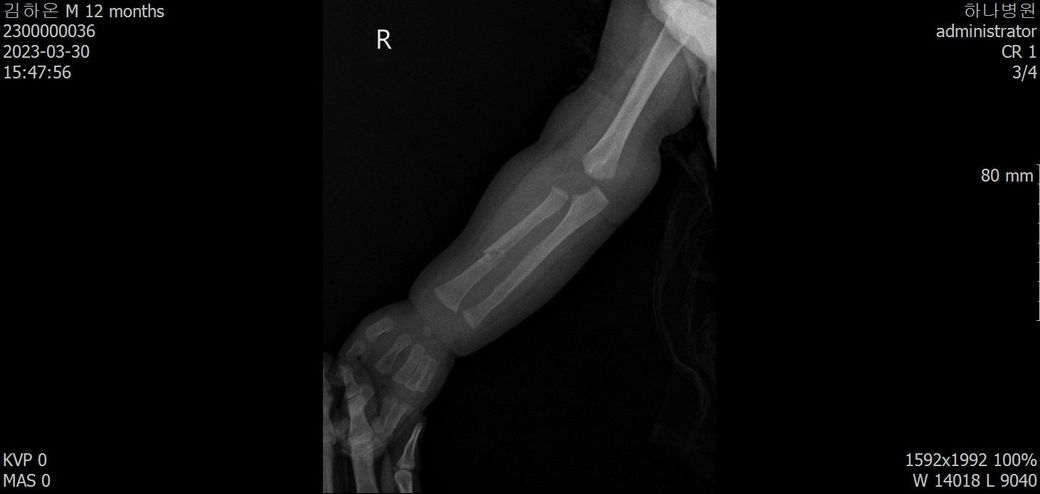

3월 30일 기준으로는 몇 일(또는 몇 주) 정도 전에 골절이 되었을 지 궁금합니다.

어떤 의사분 발언에 의하면 첨부된 4월 10일 x-ray사진처럼 유합직전의 다량의 칼러스가 발생되었다고 합니다.

아래에 3월 30일 x-ray 사진 2개, 4월 10일 X-ray 사진 2개 씩 첨부드립니다.

첨부된 사진에 X-raY 촬영 날짜가 기재되어 있습니다.

Dating fractures in infants, Clinical Radiology., Volume 66, Issue 11, November 2011, Pages 1049-1054 문헌을 보면 뚜렷한 가골 (callus)은 수상 20일쯤 확인되는걸 알 수 있습니다. 올려주신 사진을 보면 04.10에는 뚜렷한 가골이 관찰되기 때문에 20일 전인 03.20 이전일 거라고 예상이 됩니다. 03.30 X-ray에는 가골이 전혀 확인되지 않기 때문에 03.10 이후일 가능성이 높아보이고 03.10~03.20 사이가 가장 가능성이 높지 않을까 생각됩니다.